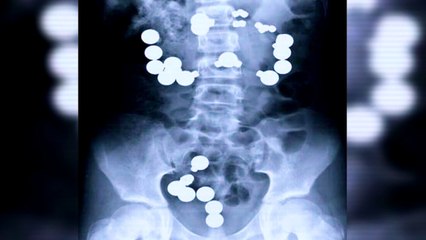

Strange things found living inside a human body sounds like a popular theme for horror stories and various urban legends and people seem to be fascinated by it. Aptly enough, there have been a few actual cases of people having some unwelcome guests reside in their bodies.